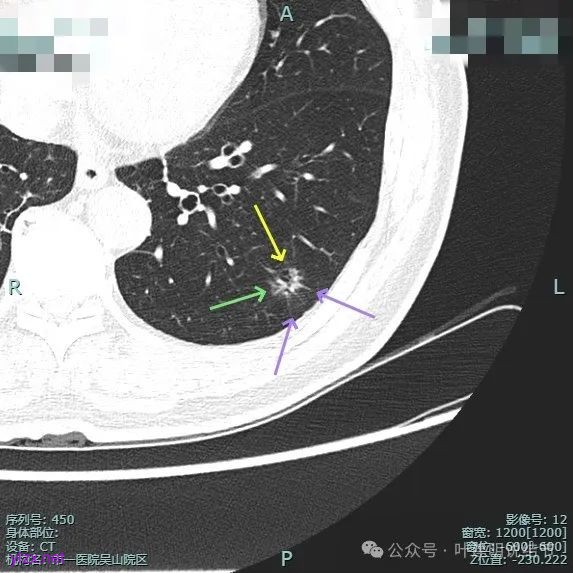

病灶毛刺空泡(或细支气管扩张)都有,表面不平,灶内杂乱。

但纵向看是偏条状些的,密度较高,边上有少许磨玻璃成分,磨玻璃部分略显模糊。

中间实性部分密度过高,边上的的毛刺显得过长,且不太锐利。

实性成分密度较高,边上有淡磨玻璃成分,毛刺明显。

密度高,边上磨玻璃成分淡,表面不平,毛刺不太锐利,整体感觉缺乏收缩力。

相应支气管有扩张,边上的磨玻璃成分偏糊,界限欠清。

进入的血管没有异常增粗,棘突不太锐利,磨玻璃成分偏糊。

上图倒是血管显得有点异常增粗的,总体膨胀性不强,收缩力不够。